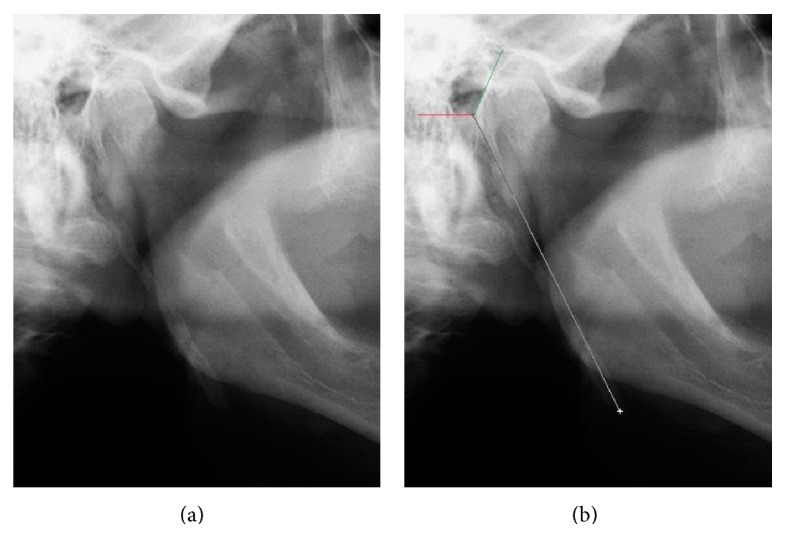

This work aimed to evaluate the occurrence of suggestive images of styloid process elongation in panoramic radiographs, noting their frequency according to sex, age, and location, as well as measure and classify the types and patterns of calcification of elongated styloid processes. 2,500 panoramic radiographs were evaluated in a Radiology Clinic in Recife, PE, Brazil, performed between 2008 and 2010, with the age ranging from 25 to 80 years old. 560 of the radiographs analyzed fulfilled the inclusion criteria. Of this total, 216 (38.57%) presented suggestive images of the styloid process elongation, 45 (20.8%) belonging to male and 171 (79.2%) to female, and 84.7% were bilateral. After all measurements, mean values of 35.5 mm (left side) and 37.6 mm (right side) were obtained and these differences were statistically significant (p < 0.001). The most common type of stretching found was elongated (type I) with 73.1%, and the pattern of calcification was partially calcified (62.5%). It was found that the elongation of the styloid process is an anatomical variation, which must be taken into account by dentists, and because panoramic radiography is a technique of easy approach and low cost and routine, it can be used to aid in the diagnosis of elongated styloid process.